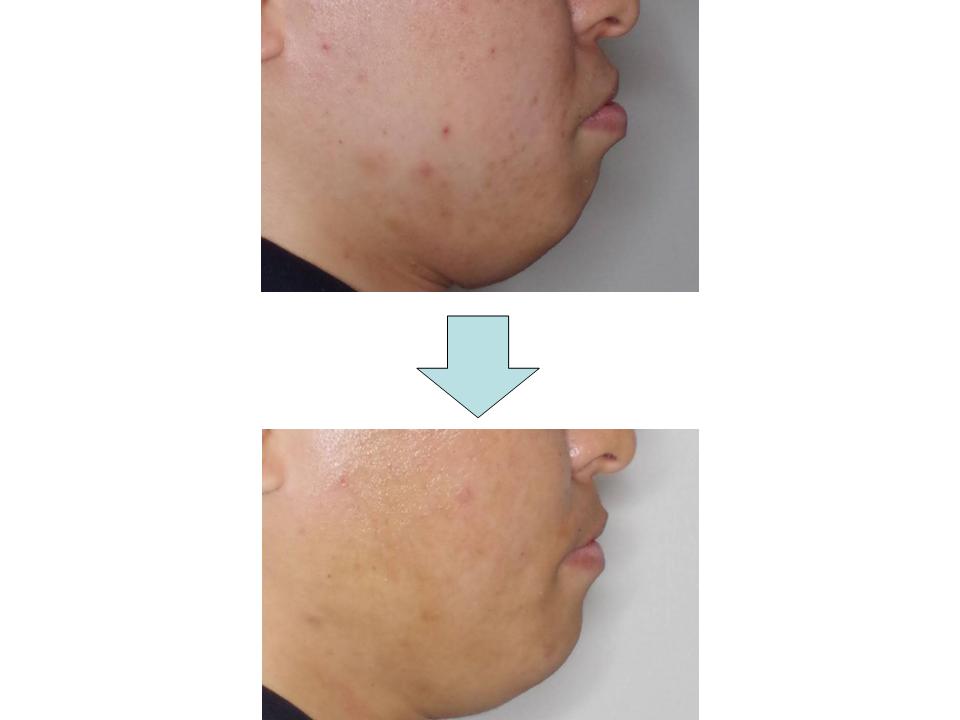

上下の歯の真ん中のずれ

上下の歯が噛んでいない状態で、治療時の歯の動きによっては抜歯や外科手術を併用する可能性をお伝えして治療を行いました。ワイヤーで歯の凸凹を並べ、上下の歯の大まかな移動を行いながら歯並びに影響する不良習癖を取り除く練習(筋機能訓練)を行い、仕上げにマウスピース型矯正装置で配列を行いました。癖の排除や装置の切り替えなどで治療期間が延び患者さんも治療途中より遠方から通院することになりましたが、最終的に上下の歯の真ん中が一致しすべての歯がきちんと並ぶ美しいかみ合わせにすることができました。

| 主訴 | 上下の歯の真ん中のずれ |

| 年齢・性別 | 43歳 / 女性 |

| 抜歯部位 | 非抜歯 |

| 装置 | メタルブラケット→マウスピース型矯正装置(インビザライン) |

| 期間 | 3年10か月 |